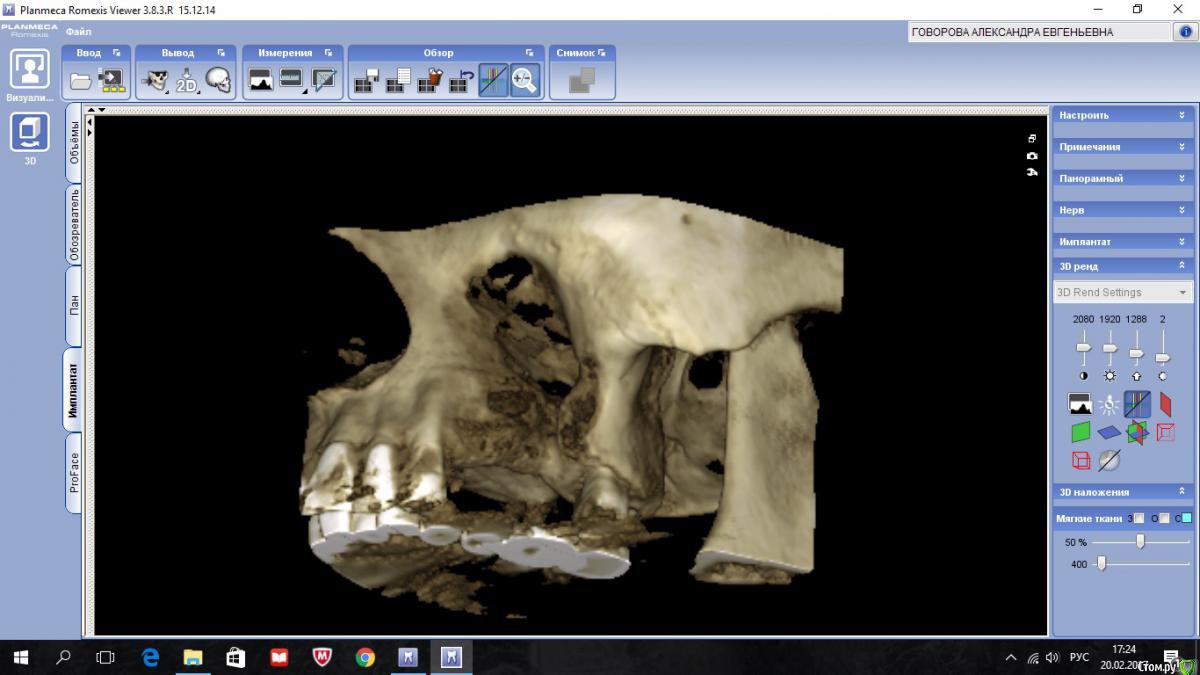

kriokov Опубликовано 20 февраля, 2017 Автор Поделиться Опубликовано 20 февраля, 2017 А разве Колдуэлл-Люк тут сильно виноват?не знаю, смотря что кто видит на снимках. Изначально--клиники синусита не было, смотрел пациентку на предмет иплантации во 2 сегменте, увидел рентгенологически тень с куполом в пазухе слева, 26 был живой на тот момент, отправил к лорикам, лорики в чло, кафедральные посмотрели- отпунктировали, вроде как получили кистозное наше содержимое. Соперировали.Посмотрел ее через месяц после гайморотомии. Нос дышал, чувствительность выпала, парус во рту по своду, но не критично. Решил подождать 6 мес.И вот сейчас картина -- клиники гайморита нет, дышит. Чувствительности нет, не восстановилась. По своду понятно- все как было. А вот рентгенологически картинка интересная-- там где не закрывалось латеральное окно, мягкие ткани туда и ввалились (наверное что на подобие рубцовых тканей), киста судя по всему была, как раз почти по верхней границе купола идет рост новообразованной кости. Кость по высоте 10-12 мм в обл 24 , 25, 26. Кто виноват (Колдуэлл или Пушкин) мне по барабану, я не эксперт, и не кафедральный. Думаю, если бы была возможность латеральное окно сеткой или мембраной перекрыть, пролапса мягких тканей внутрь не было бы. Ну и из разряда экзотики-- можно и на одном столе отработать члх и лорику. ИМХО 2 Ссылка на комментарий

kriokov Опубликовано 22 февраля, 2017 Автор Поделиться Опубликовано 22 февраля, 2017 вопрос основной как работать дальше с пациенткой. 1. носовое дыхание свободное2. естественное соустье работает, дырка в нижнем носовом тоже не заросла3. лор посмотрел -- дал заключение, что это не та патология, которую ЛОРики пользуют4. болты вкрутить- не вопрос, как понимаетеЧего делать с дырой?Варианты -- 1. соперировать, -- убрать мягкие ткани аккуратно из пазухи, поставить или фольгу или сетку-- окно то закрою конечно, заоодно гляну чего с подглазничным, на кт отверстия не видать , или снесено, или просто не визуализируется. НО , но, но- останется имеющаяся контрапертура в нижний носовой. Через год , полтора, может появиться симптоматика , как у пациентов после радикальной2. не трогать ничего, поставить болты.Буду говорить с пациенткой Ссылка на комментарий

kriokov Опубликовано 27 февраля, 2017 Автор Поделиться Опубликовано 27 февраля, 2017 Я не очень понимаю зачем пробовать востанавливать переднюю стенку пазухи. И уж тем более пробовать искать подглазничный. Будь у меня на руках эта картина вкрутил бы куда и что можно и все. Вообще очень странная история. Ну кто сегодня так радикально гайморотомию делает? Я думал К-Л уже только в учебниках встретить можно... Что доступ, что соустье в нижнем носовом огромные. 1. дырочка "совсем незначительная" осталась в пазуху + пролапс, отсюда и расссматривался вариант саблю заточить2. найти подглазничное и выделить стволик- если Вы реформат 3Д смотрели, можно думаю, ревизия не проблема. Восстановиться или нет чувствительность?- и без операции восстановиться.Поэтому не принципиально.3.Чего здесь странного, снесли переднию стенку, вход в нос через нижний, -- в Питере члх только эндоскопически чтоли на синус ходят? Конечно полегче бы хотелось, чего уж там.В малюсеньком городке Фулда (неметчина) в чло с 1980 г в пузуху (пазухи) только эндоскопом . Во Франции с 1983 только эндоскопически.Можно не обсуждать больше эту тему- вкручиваем имплантаты- и алес гутте. Ссылка на комментарий